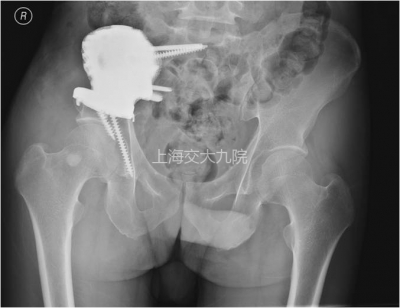

图4 术后X线片。右上图示下方两枚螺钉正好固定于髋臼前、后壁且未进入关节间隙,骶骨下方的突起与锁定螺钉有助于将剪切应力转变为压应力,骶骨上部的两枚螺钉避开了骶神经